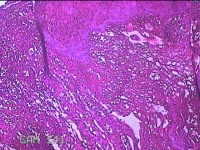

下唇肿物

性别

男

年龄

22岁

临床诊断

口腔黏液腺囊肿

下唇肿物一个月余。

大体所见

图2